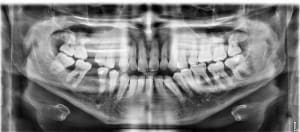

20-04-2021 Panoramique Début.JPG